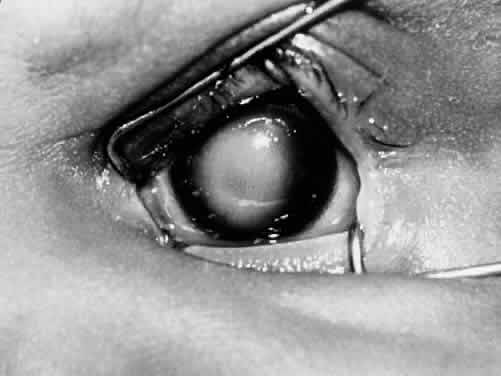

CONGENITAL CYSTIC EYE

Congenital cystic eye results when the optic vesicle fails to invaginate.2 When invagination does not occur, the development of the entire globe is arrested, and the ectodermal elements (what will become the cornea and lens placode) do not differentiate. Instead of a globe, the orbit contains a cyst, which may be either unicameral or subdivided into several loculi.29 If the congenital cystic eye is very small, it may be confused with clinical anophthalmia (see earlier discussion). Congenital cystic eyes may also be confused clinically with the condition of microphthalmos with cyst, in which the cyst is so large that it dwarfs the severely microphthalmic component.

Microphthalmos with cyst results from proliferation of neuroectoderm at the edge of a persistent embryonic fissure. The cavity of the cyst is continuous with the interior of the microphthalmic globe.2,46 Rudimentary optic nerve fibers can be seen within the cyst wall.47 The microphthalmic eye itself is often overshadowed by the larger orbital cyst (Fig. 5).48 Cases of extreme microphthalmos may be confused with anophthalmia.49,50 The anterior segment of the microphthalmic eye may appear normal, although it commonly displays marked disorganization and iridocorneal adhesions. The lens is frequently cataractous and dislocated.51 The retina is usually detached, disorganized, and gliotic.52 No consistent -association has been documented between mi-crophthalmos with cyst and a specific systemic anomaly. Systemic disorders reported with microphthalmos with cyst include central nervous -system defects (e.g., meningoencephalocele, hydrocephalus) and cardiac, urogenital, facial, and skeletal abnormalities.53–55

Fig. 5. The structure visible on the right side is the cyst component of microphthalmos with cyst. (AFIP #220948; courtesy of Torrence A. Makley, Jr, MD)